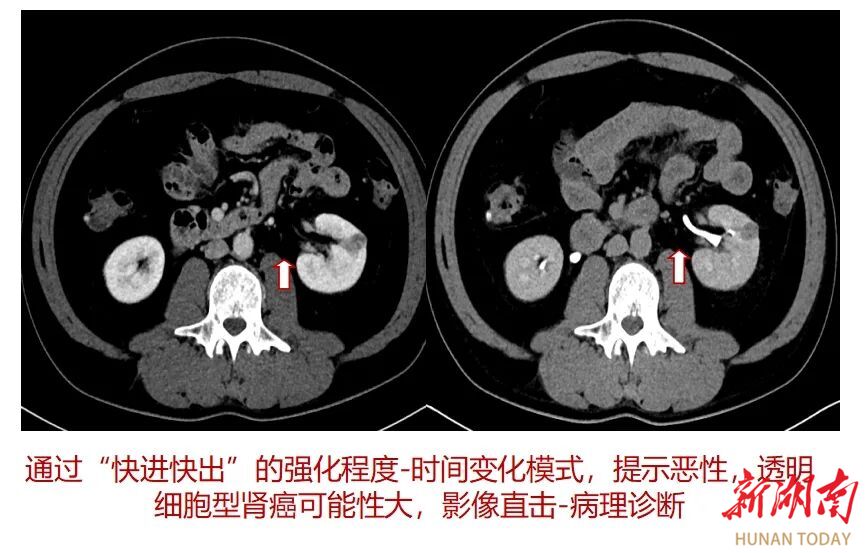

增强CT是指静脉内注射一种“药物”(有机碘对比剂)后进行不同时期扫描的方法,有利于发现平扫未显示或显示不清的病变,通过有无强化、强化—时间变化曲线,有助于病变的定位、定性诊断;通俗来说就是利用外源性对比剂来加强病灶与邻近正常组织间的密度差对比(黑与白),便于医生识别黑白世界背后的真相(找到病因)。

二、鉴别病变性质,提高疾病诊断效能